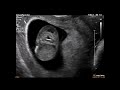

КОГДА БЕРЕМЕННАЯ ЖЕНЩИНА ДОЛЖНА ОСОБЕННО ОБЕРЕГАТЬСЯ ОТ ВРЕДОНОСНЫХ ФАКТОРОВ И БОЛЕЗНЕЙ

Когда беременная женщина ожидает ребенка, ее здоровье и благополучие становятся особенно важными. Во время беременности, она должна оберегаться от вредоносных факторов и болезней, которые могут негативно влиять на развитие малыша.